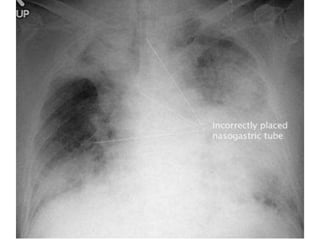

Malpositioned chest drain: the side-holeof the drain lies outside the pleural cavity